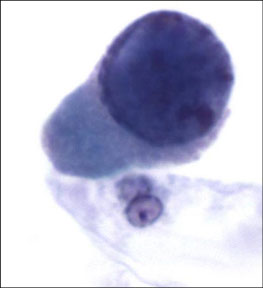

Polyomavirus

Polyomaviruses (JC and BK viruses) commonly affect urothelial cells of both healthy and immunocompromised individuals. Characteristic viral cytopathic changes are seen in 4% of urine samples. The infection usually has no clinical significance, except in immunocompromised (transplant) patients

- nickname is "decoy cells"

Cyto: Infected urothelial cells have large eccentrically placed nuclei with basophilic nuclear inclusions that completely replace the nucleus and appear glassy, opaque or cloudy.

- because of increased nuclear size and hyperchromasia, these cells are sometimes confused with malignant cells – hence their pseudonym “decoy cells”. However unlike most malignant cells , decoy cells have perfectly smooth and round nuclei.

IHC: (+) SV 40